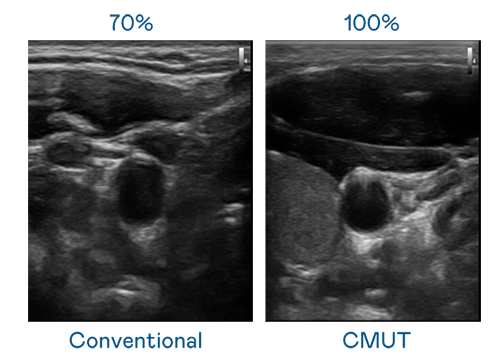

CMUT technology utilizes capacitive MEMS components to generate ultrasound signals. Compared to traditional ceramic piezoelectric technology, the 30% increased bandwidth of CMUT allows for wider ultrasound signals and greatly improved image resolution. This is a crucial technology for achieving medical ultrasounds with high-quality images and promoting the development of precision medicine.

• Ultra-wide bandwidth offers high-quality images

The image quality of medical ultrasound depends on the signal bandwidth the ultrasound transducer can emit. AUO's CMUT offers high-resolution ultrasound signals with ultra-wide bandwi